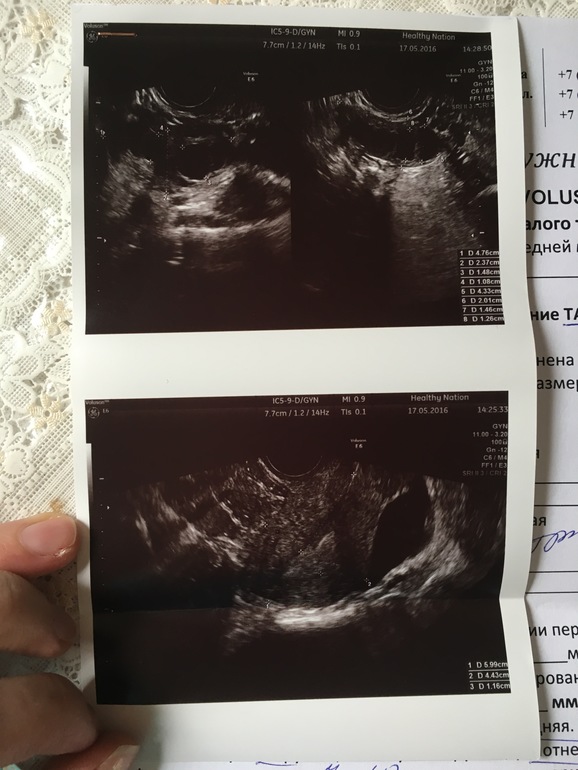

Узи на 11 д.ц

Вырастил дивигель мне хороший такой эндометрий , 11 мм на 11 д.ц, фолликулы в левом и в правом яичнике по 15 мм, жидкость есть в позадиматочнои пространстве , а жт нет 🙄 Может не было у меня ещё овуляции ? Откуда жидкость то тогда 😑 Не хочу я чтоб оказалось так , что она уже была , у нас после мес ПА только вчера был, мы так ничерта не успеем 😭😭😭😭

жт нет значит О не было... фоллики 2 штуки по 15 .... значит дня 3-4 до О

Жидкость до овуляции может быть из за воспаления, эндометриоза или просто вариантом нормы) а толщина эндометрия не соответствует дню цикла, потому что 11мм до овуляции это многовато, учитывая, что фолликулы еще всего 15мм. И к тому же контуры не четкие. Лучше после овуляции переделать узи.